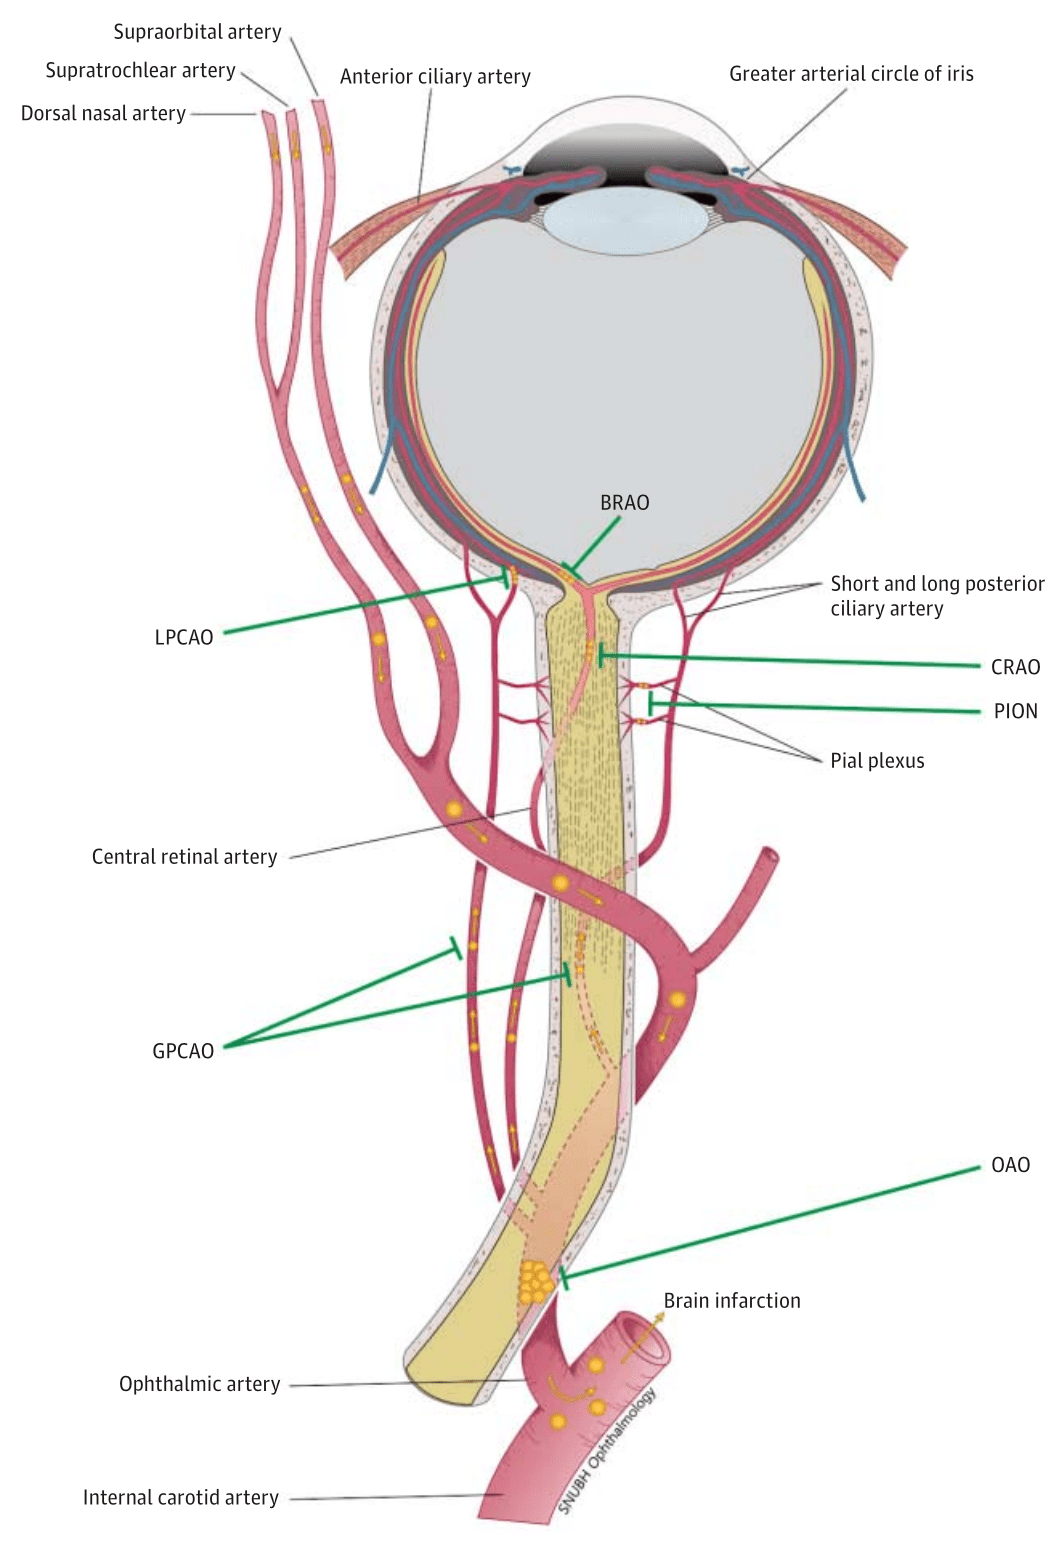

经滑车上动脉逆行或颈外动脉顺行介入溶栓治疗视网膜中央动脉阻塞伴同

发病机制眼动脉的分支有睫状前动脉,睫状后动脉,泪腺动脉,滑车上动脉

经滑车上动脉逆行或颈外动脉顺行介入溶栓治疗视网膜中央动脉阻塞伴同

【惟视诊室】面部注射玻尿酸,1小时后失明!

同时,鼻部的血液供应非常丰富,鼻子的血管贯穿面部构成了复杂而广泛的

视神经的外侧,然后在上直肌的下方越至眼眶的内侧前行,终于滑车上动脉